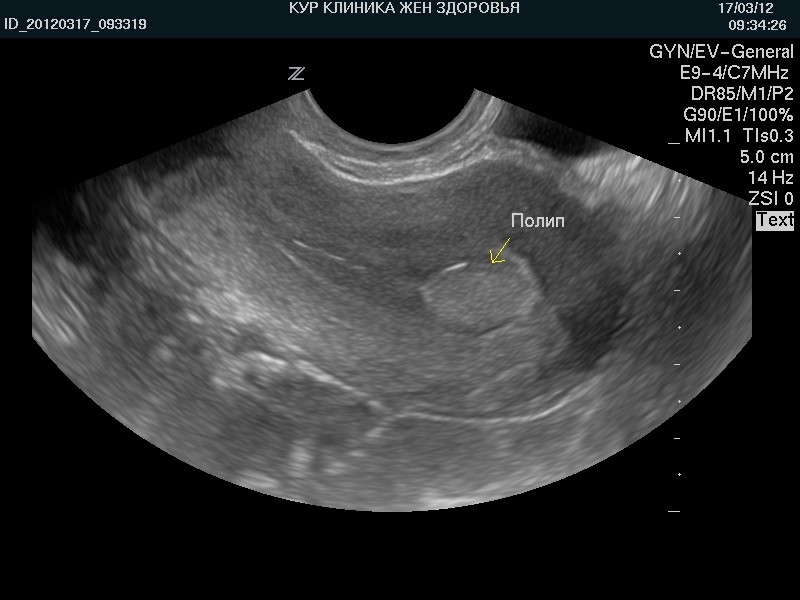

Медицинская диагностика: Гиперплазия эндометрия на УЗИ